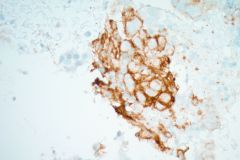

Specimen Type: FNA Station 4L, 4R Lymph Nodes, Modified Romanowsky smears, Papanicolaou smears, Thin Prep® Non-Gyn slide, H&E Cellient® Cell Block

Biopsy/Pathologic Diagnosis: Corresponding Surgical Pathology H&E Slides of Core Biopsy of 4R Lymph Node, Positive for Malignancy, Adenocarcinoma with malignant cells staining positive for TTF-1 and negative for GATA3 and SOX10. PD-L1 immunohistochemical staining is positive.

When reviewing the slides cytologically, there is moderate to high cellularity, with malignant cells present in three-dimensional cohesive groups as well as scattered single cells.1,7 Compared to the background population, these cells appear enlarged and demonstrate increased nuclear-to-cytoplasmic ratios, irregular nuclear borders and contours, and prominent nucleoli with variable chromatin patterns.1 Nuclear pleomorphism is present, and occasional multinucleated tumor cells can be identified.1 The cytoplasm is moderate in amount and appears vacuolated due to mucin production, which reflects glandular differentiation with extracellular mucin and necrotic debris present in the background.1,2 Overall, these cytologic findings are characteristic of an epithelial glandular cell malignancy. Because adenocarcinoma shares overlapping cytologic features with other poorly differentiated tumors, IHC stains such as TTF-1 and Napsin A are used to help confirm pulmonary origin.1,7

Given the patient’s prior clinical history of breast cancer, metastatic breast adenocarcinoma was an important differential diagnosis to consider. Cytologically, metastatic breast adenocarcinoma can present with cohesive clusters of epithelial cells, enlarged nuclei, and prominent nucleoli, which may overlap with the appearance of lung adenocarcinoma.9 Because these tumors may share similar glandular morphology, IHC staining is often necessary to determine the primary site. Breast adenocarcinoma typically demonstrates positivity for markers such as estrogen receptor (ER), progesterone receptor (PR), GATA3, and mammaglobin.9

Metastatic melanoma was also an important consideration given the patient’s history. Melanoma may show pleomorphic cells with prominent nucleoli, abundant cytoplasm, and variable cellular cohesion, which can sometimes resemble poorly differentiated carcinoma on cytologic preparations.10 Because melanoma demonstrates wide morphologic variability, immunohistochemical stains are essential for diagnosis. Melanoma typically shows positivity for markers including S100, SOX10, HMB-45, and Melan-A, which help distinguish it from epithelial malignancies.10